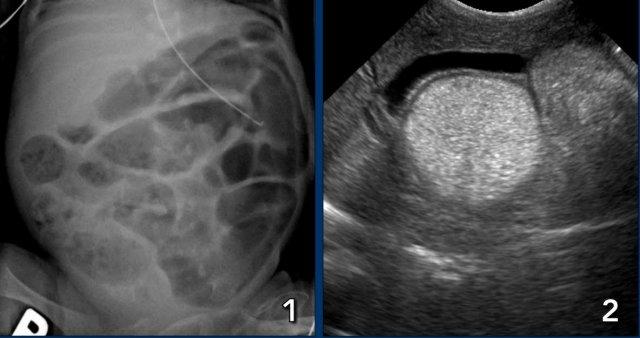

Hình ảnh

X-quang bụng cho thấy các quai ruột giãn và phân bố hơi không đều với vùng thiếu hơi ở góc phần tư dưới phải.

Hai phim X-quang chụp cách nhau vài giờ cho thấy ở vùng bụng trên chỉ có các quai ruột giãn nhẹ nhưng không có nếp niêm mạc, không thay đổi theo thời gian. Đây là dấu hiệu của vắng mặt nhu động ruột.

Một ví dụ khác về quai ruột cố định.